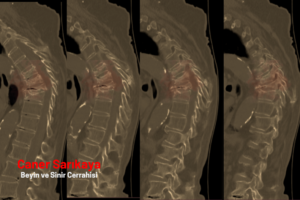

2. Bilgisayarlı Tomografi (BT)

- Kırığın şekli, yönü ve yayılımı hakkında detaylı bilgi sunar.

- Röntgende görülmeyen küçük kırıkları tespit eder.

- Cerrahi planlama yapılacaksa mutlaka kullanılır.